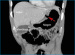

Abbildung 3: Lungenfenster Die Rekonstruktion der CT-Bilder im sogenannten "Lungenfenster" zeigt anschaulich die Luftansammlungen in der Peritonealhöhle. Das Ligamentum falciforme der Leber ist von Luft umgeben (Pfeile). |

Die Rekonstruktion der CT-Bilder im sogenannten "Lungenfenster" zeigt anschaulich die Luftansammlungen in der Peritonealhöhle. Das Ligamentum falciforme der Leber ist von Luft umgeben (Pfeile). |